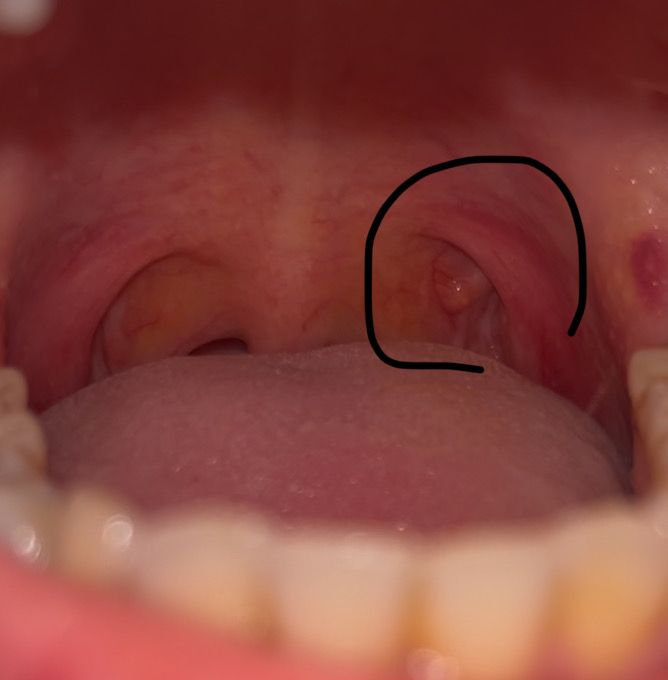

목젖옆에 튀어나온게 있어요....

3일전 사랑니 발치를 해서 입안을 보다가 갑자기 목젖옆에 튀어나온걸 발견했어요.. 아무 느낌도 없었는데 이게 뭘까요? 병원가야하는건가요? 그러고보니까 침삼킬 때 그쪽이 좀 따갖게 불편한것같긴 한데 엄청 아프거나 그러진않아요

일시적으로 편도 근처에 염증이 생겨 부은 것이나 이번 기회를 통해 우연히 발견한 것 일수 있습니다.

일주일 이상 지나도 증상이 유지되거나 통증이 동반된다면 병원에 방문권유 드립니다.